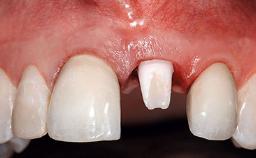

A 30-year-old patient presented at our clinic with a chief complaint of pain in her endodontically treated right maxillary central incisor (tooth 11) with a post-and-core and a fixed single crown. She had a very high lip line, a medium to thin soft-tissue phenotype, and a medium scalloped gingival contour. She also had high esthetic expectations because of her young age and beautiful smile. However, her expectations were realistic and she understood the risks of the treatment. At the initial clinical examination there was a slight mobility of tooth 11; no fistula was observed. The patient also had a single crown on the adjacent tooth 21. Both restorations were old and esthetically deficient. A digital periapical radiograph showed a very small periapical radiolucency, a thick intraradicular post, and no separation between root fragments.

Prosthesis Type FDP